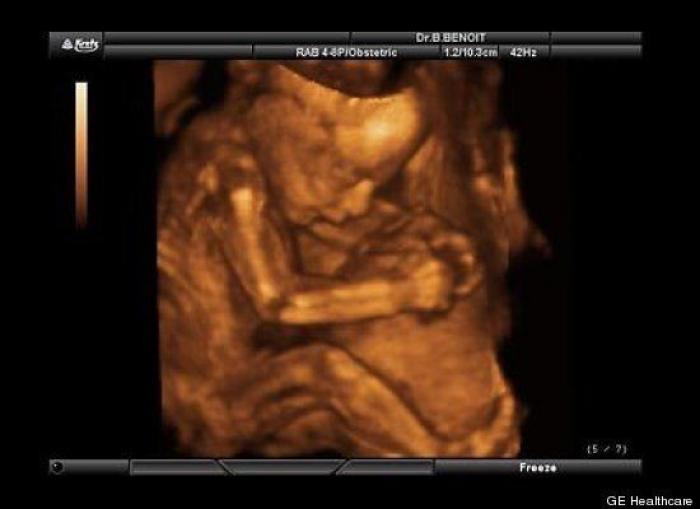

En esta galería puedes ver en fotos como es el desarrollo de un feto de semana en semana:

Desarrollo del feto, en fotos

Ver la galería